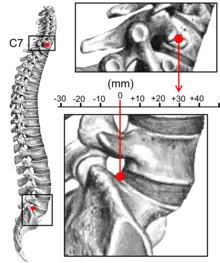

Kyphosis can be graded in severity by the Cobb angle. Also, sagittal balance can be measured. The sagittal balance is the horizontal distance between the center of C7 and the superior-posterior border of the endplate of S1 on a lateral radiograph.[15]